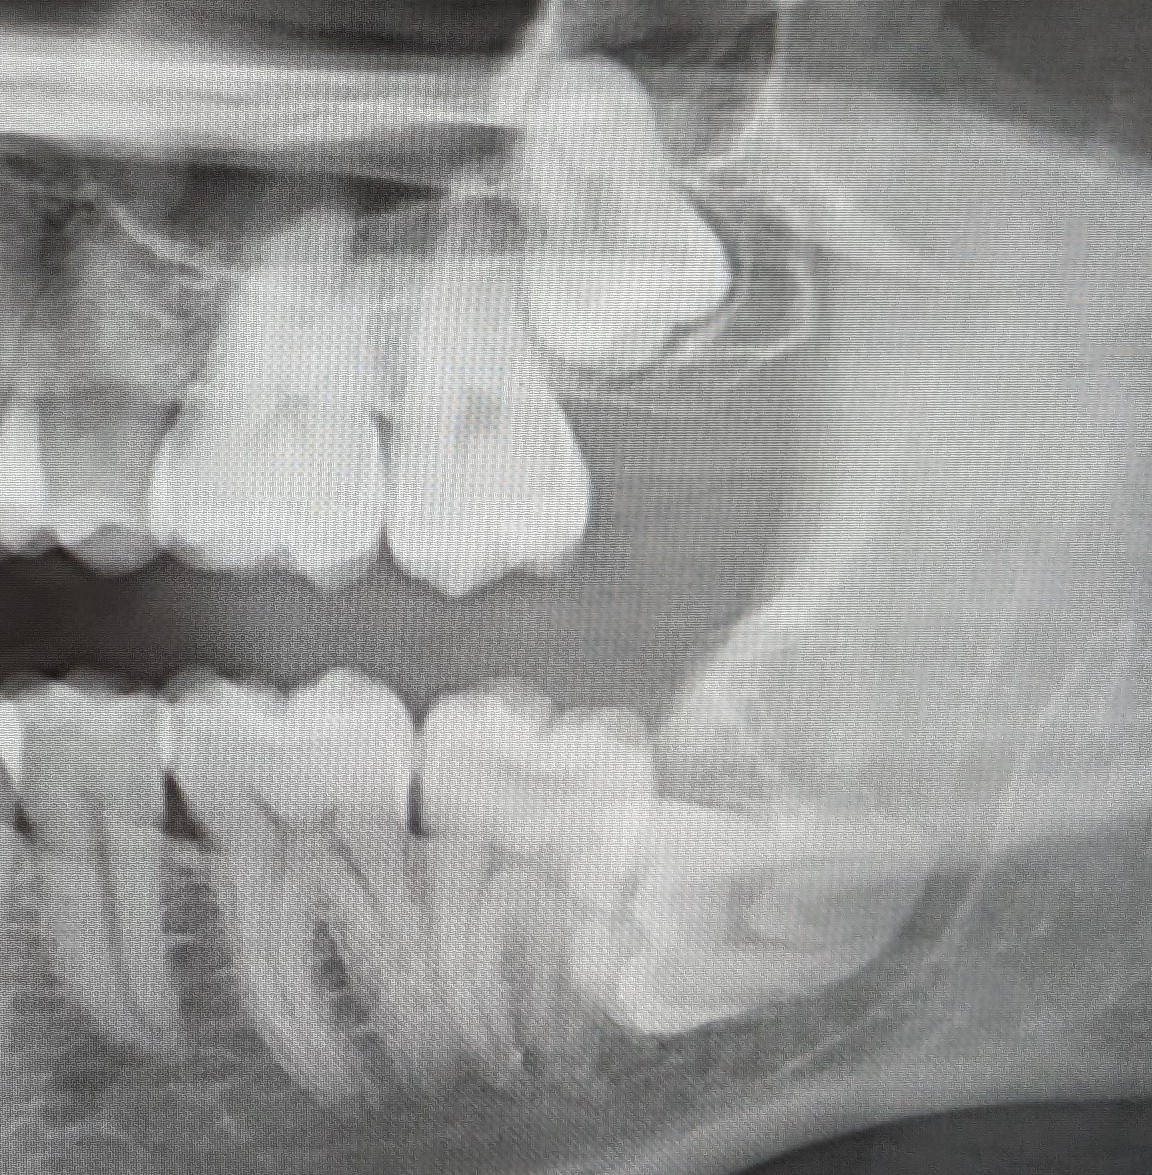

>>84428794>is it a problem though?It might upset her if she found out I think that. Although I'm of the belief that your SO should pretty much be your best friend.>they just yank it one way then the other and it's outMakes sense. None of mine have erupted yet (they show up on x-rays) so that might be why I assumed you'd go under the knife for it.>I'd say it's better to always act like that every when they're notTrue. You wouldn't want to chip one by accident.

>>84430763>so who are you going to cosplay?It's classified for now but I may reveal later. >they're not coming out on their own?I'm not really sure to be honest. My old dentist said I probably won't need them removed but the one I saw most recently thinks I might need to have them taken out in the next couple of years.According to this x-ray one of them is sideways.